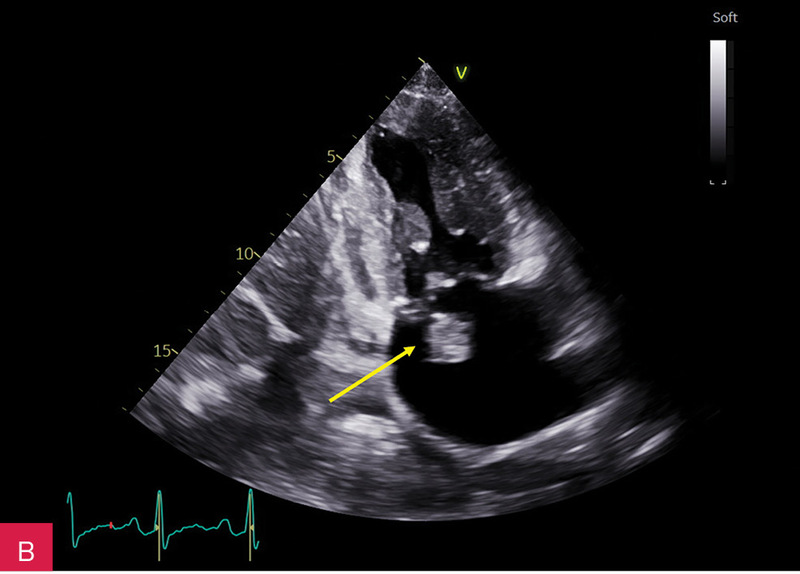

Rycina 8A, B. Obrazy rezonansu magnetycznego w projekcji pięciojamowej (A) i dwujamowej (B) z późnym wzmocnieniem kontrastowym – widoczna zmiana ulegająca brzeżnemu wzmocnieniu kontrastowemu. Całość obrazu wskazuje na serowate zwapnienie pierścienia mitralnego (CCMA)

W celu weryfikacji zmiany i oceny charakterystyki tkanki wykonano CMR,

w którym stwierdzono w dolno-bocznej części pierścienia mitralnego od strony światła lewej komory zmianę odpowiadającą morfologicznie CCMA, obejmującą 7,3 cm obwodu pierścienia mitralnego, o grubości w osi krótkiej do 25 mm, w osi długiej do 21 mm; zmiana ulegała brzeżnemu wzmocnieniu kontrastowemu i powodowała ograniczenie ruchomości tylnego płatka zastawki mitralnej, obejmowała struny ścięgniste mięśnia brodawkowatego tylno-przyśrodkowego. Ponadto uwidoczniono znacznie powiększone przedsionki z istotnym włóknieniem – jak w restrykcji (ryc. 7, 8).